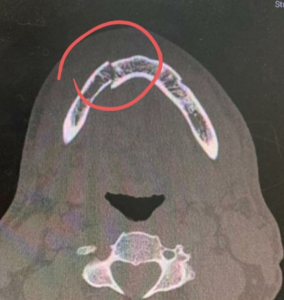

Porém, ele explica que estava em um momento com amigos, quando de repente uma pessoa chegou e o puxou pelo pescoço, em seguida, o agrediu com socos e chutes, que levou a uma fratura exposta na região da mandíbula.